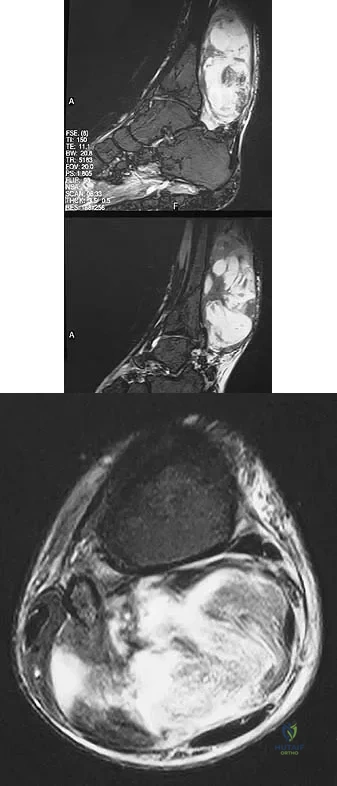

Figures 13a and 13b show the MRI scans of a 70-year-old patient who has a posterior calf mass. Examination reveals that the mass extends to the midcalf level. A biopsy specimen reveals a high-grade soft-tissue sarcoma. Metastatic work-up shows no lesions. Management should consist of

A 9-year-old boy has a painless enlarged mass on the dorsum of his hand. Figures 14a through 14d show the clinical photograph, radiographs, and biopsy specimen. What is the most likely diagnosis?